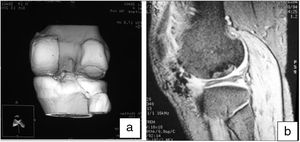

The surgical technique used comprised an internal or external knee arthrotomy, followed by preparation of the damaged area using the Maxioats® (Artrhex®) technique23 (Figs. 1 and 2).

Two patients required special milling of the graft, as the Maxioats® technique did not cover the defect; one received a double graft and, at one year, arthroscopic control of the graft (Figs. 3 and 4); in the other case, the graft was milled by hand, given the defect, and fixed with 2 Herbert screws (Figs. 5 and 6).